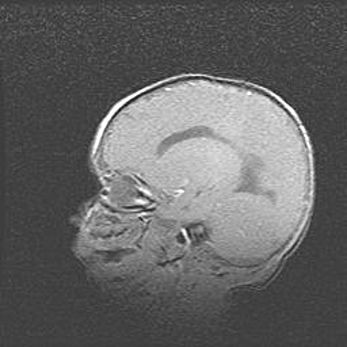

Открытая гидроцефалия.

Возраст: 9 месяцев 12 дней

Вес: 6800 г

Пол: мужской

Окружность головы: 41,5 см

Срок гестации: 28 недель

Гидроцефалия головного мозга у новорожденных имеет характерный признак: опережающий рост окружности головы приводит к визуально хорошо определяемой гидроцефальной форме сильно увеличенного в объёме черепа. Детские неврологи определяют следующие симптомы гидроцефалии у грудничков: выбухающий напряжённый родничок, частое запрокидывание головы, смещение глазных яблок к низу.